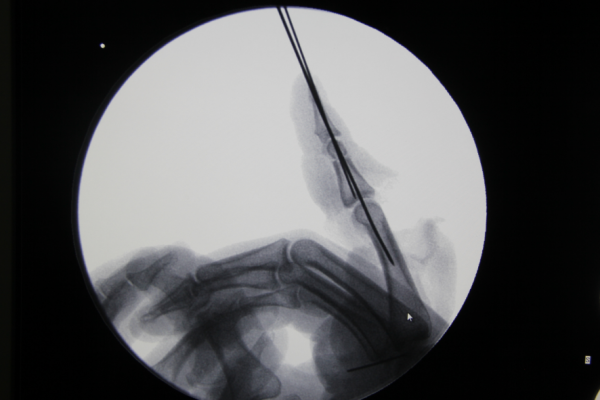

前天值班,来了7个再植的病人,初学者来省立医院进修是个很好的选择。这是其中一个。示指旋转撕脱,近侧指间关节处离断,保关节再植。

x线

QQ截图20161216215221.png QQ截图20161216215232.png

术后即刻,血管撕脱太厉害,动静脉还是移植了。